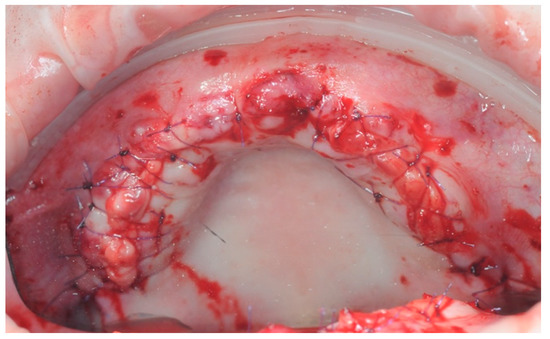

2.3. Re-Entry Surgery

3.3. Hard Tissues Gain

3.4. Soft Tissue Management